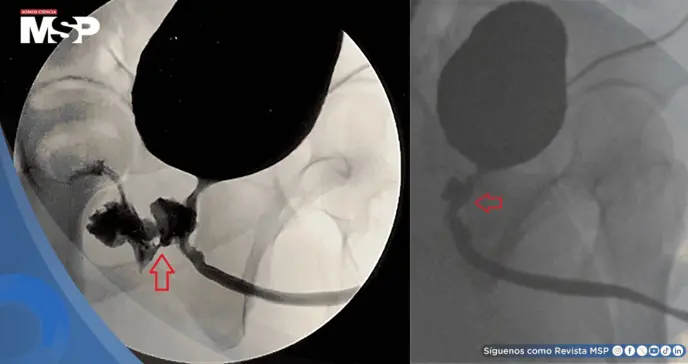

Los análisis de sangre mostraron signos de infección, al igual que un examen de orina. Para obtener una imagen más clara, se le realizó una tomografía computarizada de la pelvis, la cual reveló una infección en los testículos y, lo que es más importante, la presencia de una conexión anormal entre la próstata y el recto, lo que se conoce como fístula rectouretral.

Este pasaje, que permitía el intercambio de orina, heces y semen entre ambos órganos, tenía apariencia de ser un problema crónico.

Aunque existen diferentes métodos de imagen para diagnosticarla, la visualización directa mediante endoscopia suele ser clave. Respecto al tratamiento, si bien en contados casos seleccionados puede intentarse un manejo conservador, la gran mayoría de estas fístulas requieren una reparación quirúrgica para su solución definitiva, tal como se hizo en este caso.